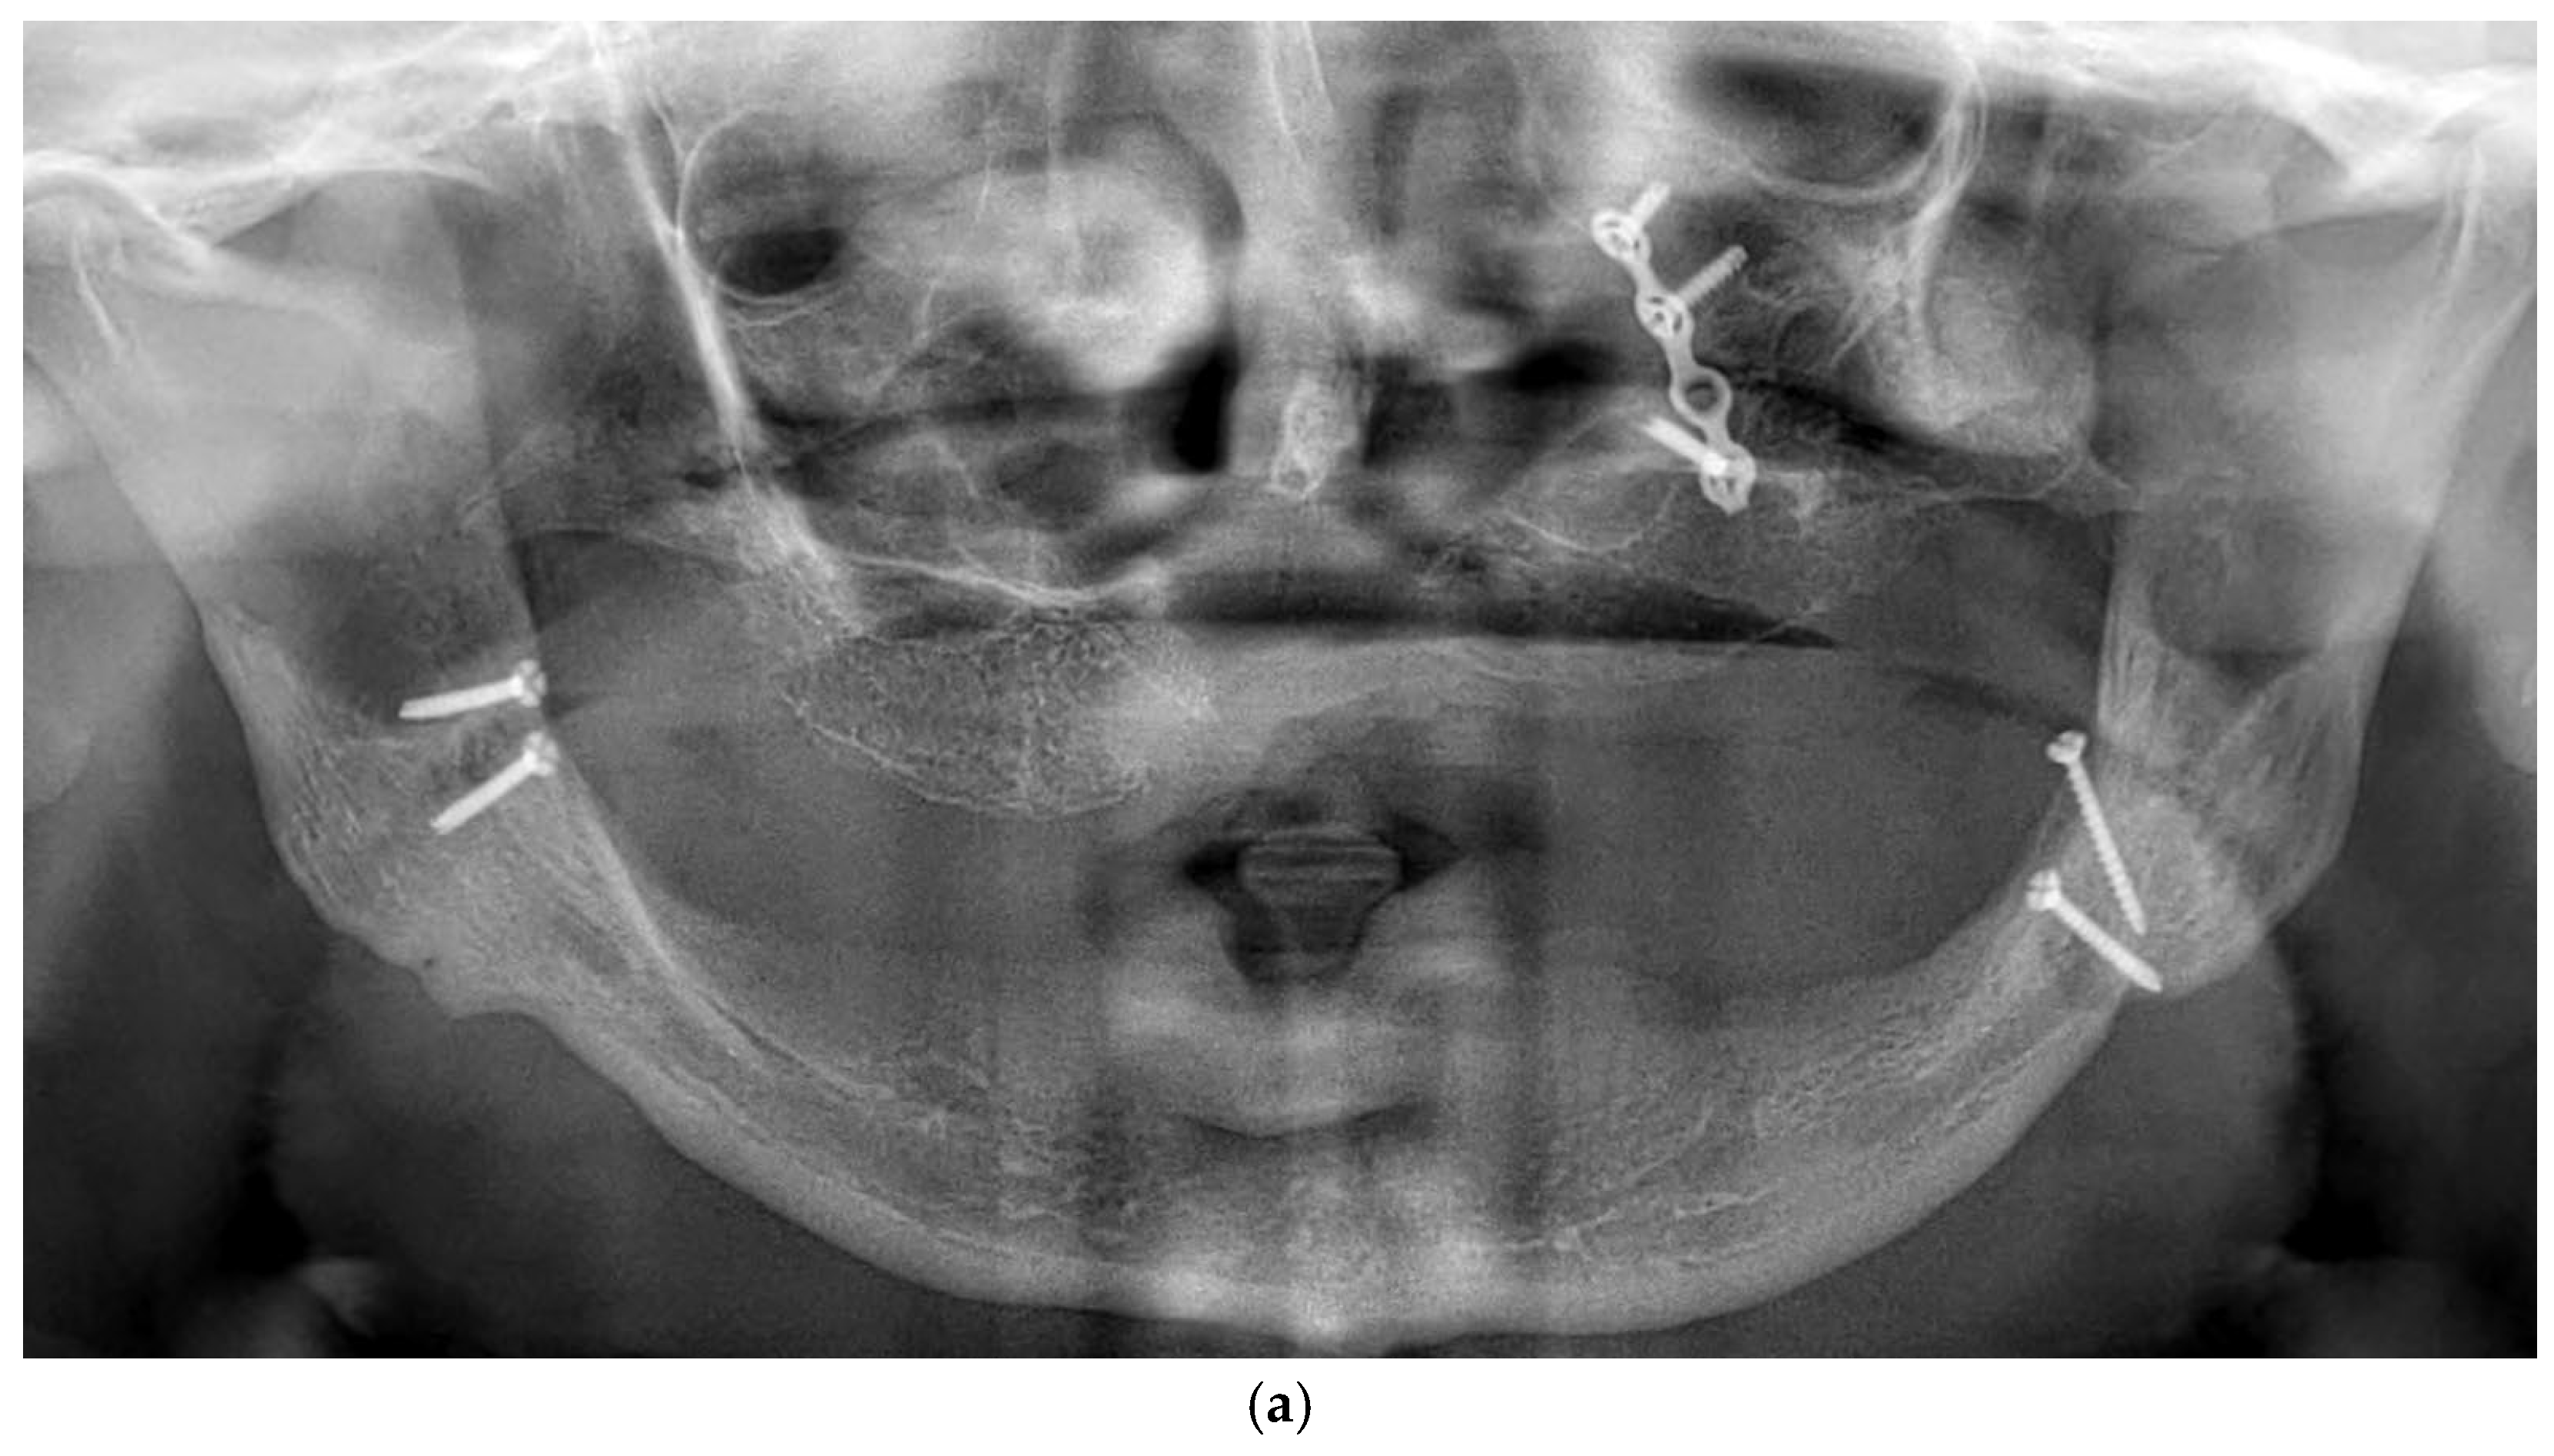

3.11. Case Series

3.11.1. Patient Demographics and Clinical Characteristics

3.11.2. Surgical and Prosthetic Protocol